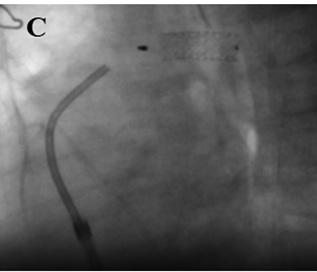

presenta nuevo episodio sincopal. Se realiza un ecocardiograma transtorácico (ETT) Doppler (Figura 1) con evidencia de dilatación de cavidades derechas; por

lo que, asociado al antecedente reciente de cirugía traumatológica, se sospecha

Fig. 1. Ecocardiograma transtorácico

al ingreso. A. Vista apical de 4 cámaras, fin de sístole. Se observa marcada

dilatación de cavidades derechas. B. Eje corto paraesternal.

Se observa la dilatación del ventrículo derecho, con aplanamiento del septum

interventricular.